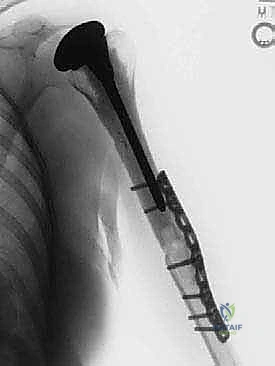

Allograft and Prosthesis Procurement

We've already contacted an AATB-accredited tissue bank to secure our frozen humeral allograft. Its radiograph has been templated against our patient's anatomy and the chosen long-stem humeral prosthetic hemiarthroplasty device. We ensured the allograft is sufficiently long to replace the resected bone and has an appropriate soft tissue cuff for later repair. We also templated the glenoid to confirm the appropriate metallic hemiarthroplasty size.

6. Bone Division

"Now for the critical bone cut. We've already isolated the humeral shaft distal to the tumor. Based on our preoperative MRI and templating, we've identified the